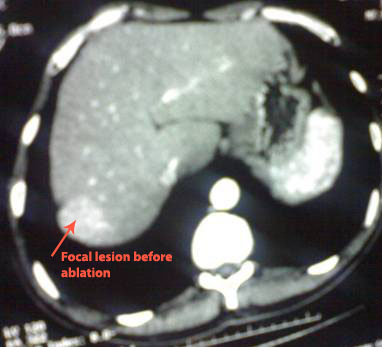

Male patient 45 year-old, chronic C hepatitis, presented with

hepatic focal lesion.

CT abdomen before radiofrequency ablation .